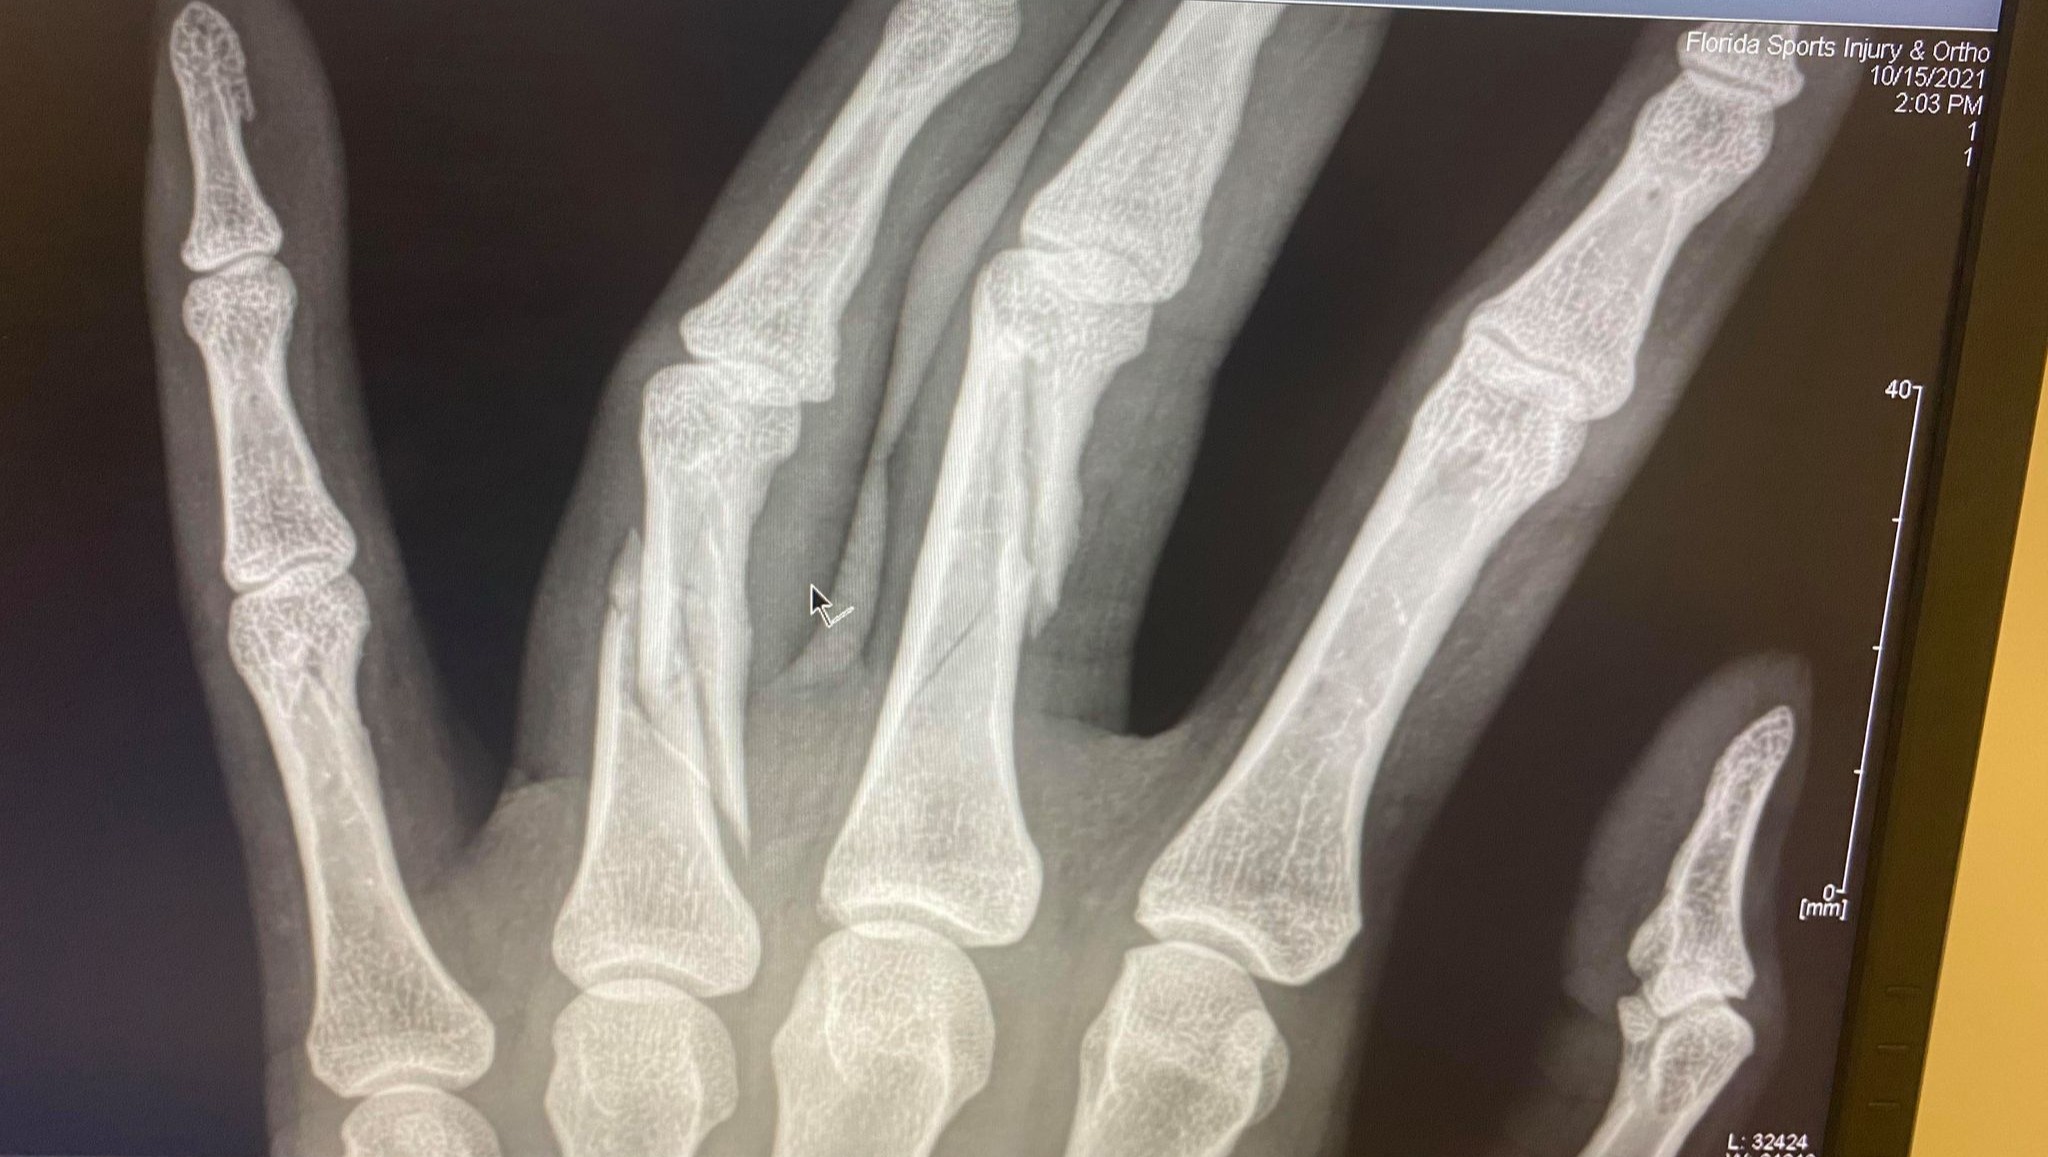

On October 7th, I was in a car crash with a semi-truck, causing multiple injuries, the most serious of which being 3 broken fingers. The injuries to my hand require surgery which will take place on October 19. Altogether, I will be in recovery from 3 - 4 months, while also recovering from an MCL tear.

Tuesday's surgery was a success. Once the surgeon began, he quickly realized the damage was more extensive than the x-rays showed. What was supposed to be a 2-hour surgery ended up taking over 6 hours. They had to reconstruct my middle and ring finger, with 11 screws and 2 pins in my pinky finger.